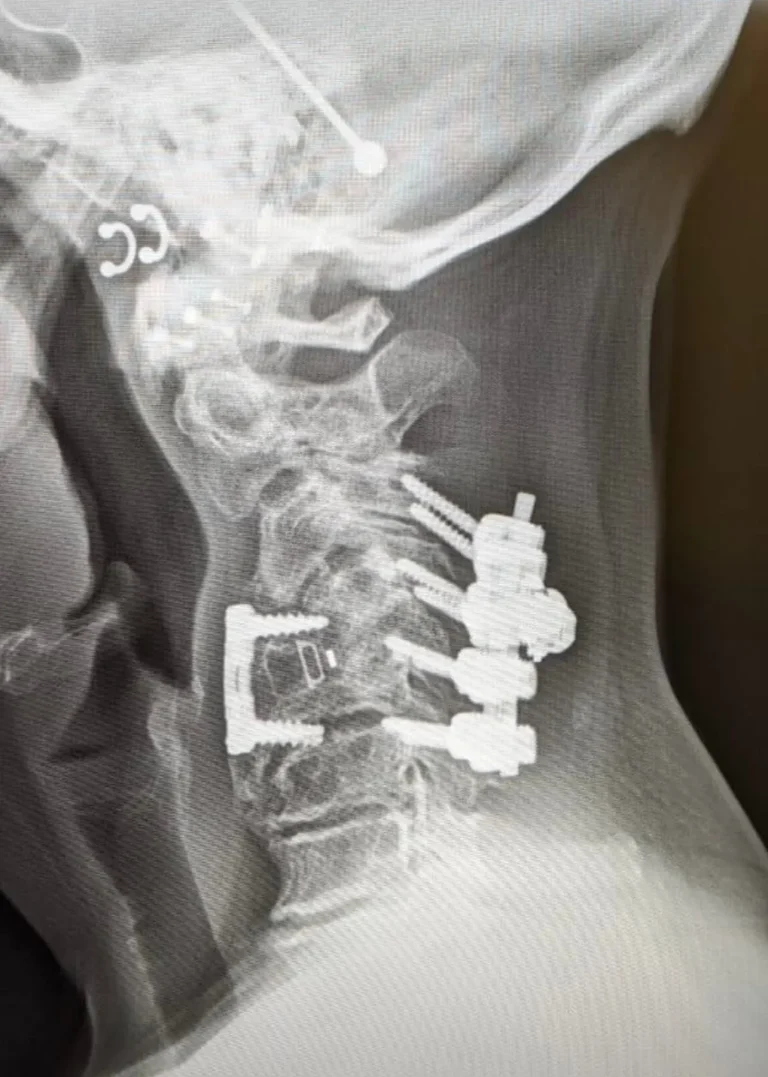

Two X-rays of a neck showing spinal screws in the vertebrae.

X-ray of a neck showing metal screws and plates in the cervical spine.

Additional Surgery Likely